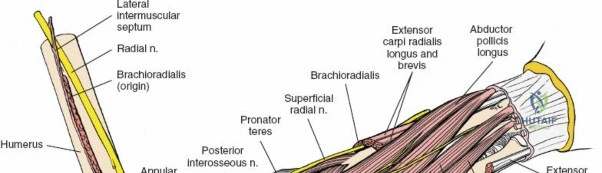

The anterior approach to the radius is an elegant example of utilizing true internervous planes to achieve deep exposure without denervating musculature. Distally, the internervous plane lies between the brachioradialis muscle (innervated by the radial nerve) and the flexor carpi radialis muscle (innervated by the median nerve). Proximally, the plane transitions to lie between the brachioradialis (radial nerve) and the pronator teres muscle (median nerve). Exploiting this plane allows the surgeon to mobilize the entire lateral muscular compartment (the "mobile wad" comprising the brachioradialis, extensor carpi radialis longus, and extensor carpi radialis brevis) away from the anterior flexor compartment.

The posterior interosseous nerve is the single most important structure left vulnerable during exposure of the proximal radius. A branch of the radial nerve, the PIN dives into the supinator muscle through the Arcade of Frohse. It travels obliquely and spirally around the radial neck and proximal shaft within the substance of the supinator. In approximately 25% of patients, the nerve comes into direct contact with the posterior periosteum of the radial neck. Therefore, any blind placement of retractors around the posterior aspect of the proximal radius is strictly contraindicated, as it can easily crush the nerve against the bone, resulting in devastating loss of finger and thumb extension.

Superficial Surgical Dissection and Internervous Plane

Incise the deep fascia of the forearm in line with the skin incision. The initial goal is to identify the medial border of the brachioradialis as it courses down the forearm. It is a common pitfall to search for this border too far laterally. At the level of the elbow, the brachioradialis is expansive and extends almost halfway across the anterior forearm. It is surprisingly easy to mistake the plane between the brachioradialis and the extensor carpi radialis longus for the correct intermuscular plane.

To confirm the correct plane, look for the superficial branch of the radial nerve. This sensory nerve runs on the undersurface of the brachioradialis muscle. Once the true medial edge of the brachioradialis is found, develop the plane between it and the pronator teres (proximally) or the flexor carpi radialis (distally). Retract the brachioradialis laterally, taking care to keep the superficial radial nerve attached to its undersurface to protect it from traction injury.